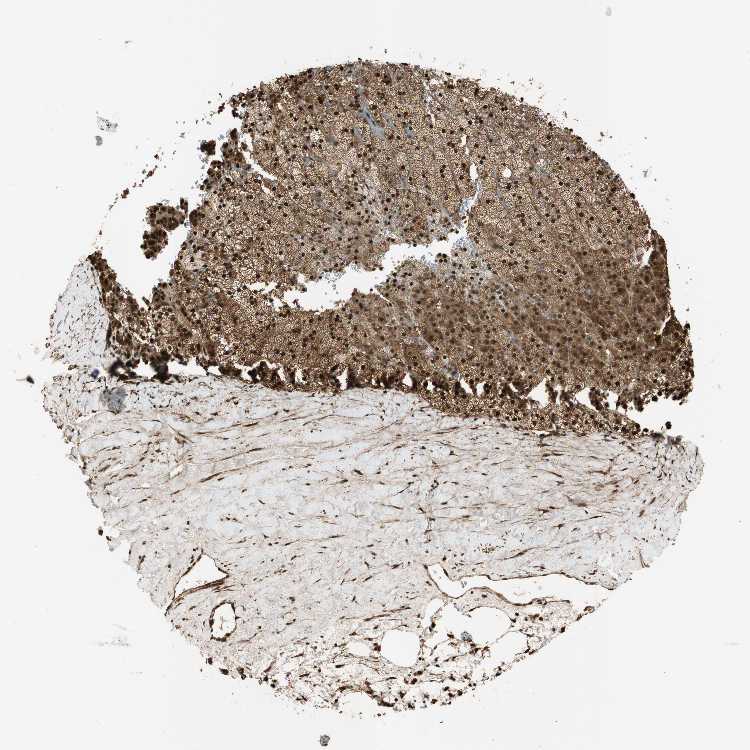

ADRENAL GLAND - Antibody stainingi

Antibody staining in the annotated cell types in the current human tissue is reported as not detected, low, medium, or high, based on conventional immunohistochemistry profiling in selected tissues. This score is based on the combination of the staining intensity and fraction of stained cells.

Each image is clickable and will lead to virtual microscopy that enables deeper exploration of all samples and also displays staining intensity scores, fraction scores and subcellular localization as well as patient and tissue information for each sample.

Antibody HPA005708

Glandular cells High